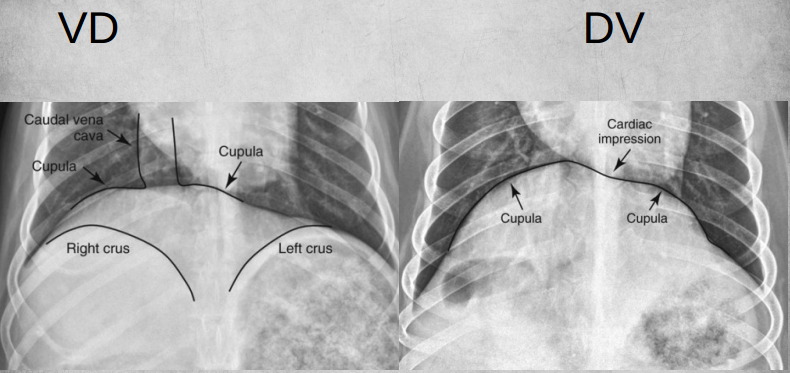

Describe differences between VD/DV thoracic views.

A

● DV

– Cardiac silhouette looks more “normal”

– Less magnification

– Caudal arteries and veins seen better

– Preferred view for cardiac patients

– Small amount of free air more easily visible.

● VD

– Preferred view for lungs

– Small amount of free fluid more easily visible